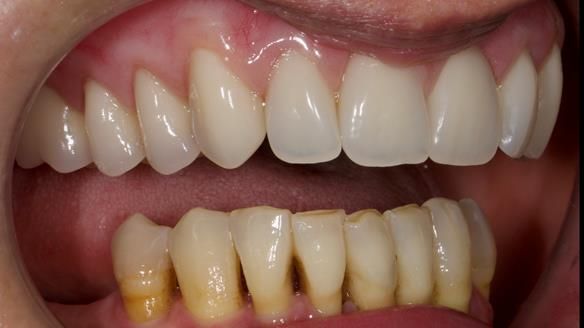

She had previously suffered from generalised periodontitis – stage IV, grade C, currently stable, with reduced attachment across the upper arch.

By the time she came to me, her periodontal condition was stable — but the aesthetics in the upper jaw were very poor.

We provided her with an immediate upper denture (Mk 1), followed by a definitive metal-based upper denture (Mk 2). A lower removable partial denture was discussed, to be made only if needed once the upper treatment was complete. However, at review, this wasn’t necessary — Adnana had excellent neuromuscular control and function, even with a shortened dental arch (SDA).